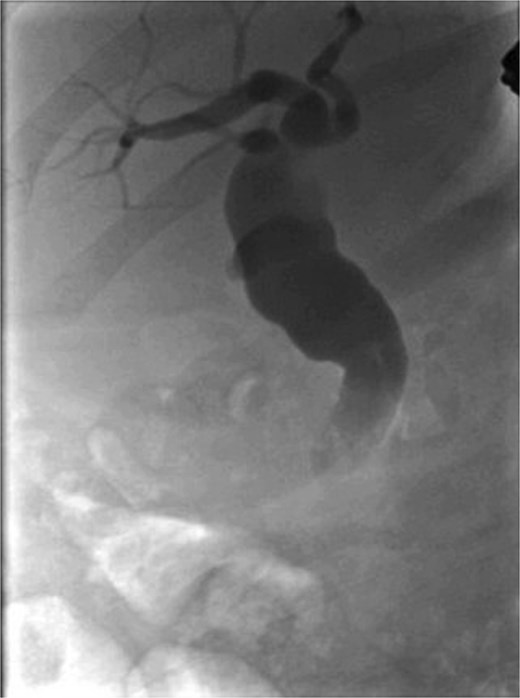

Following surgical intervention, the patient was admitted to the intensive care unit (ICU), where she was closely monitored for three days before being stepped down to the ward. During this time, her labs normalized, and drain output decreased steadily. The drain was removed on post-operative day (POD) 11, and she was subsequently discharged. Notably, the cytology of CBD brushings did not reveal any malignant cells. A repeat ERCP was performed after 8 weeks, which revealed no contrast leak, indicating spontaneous healing (Fig. 5), and the biliary stent was removed. Successive clinic follow-up at 6 months post-treatment indicated that the patient remained completely asymptomatic and exhibited excellent clinical recovery.